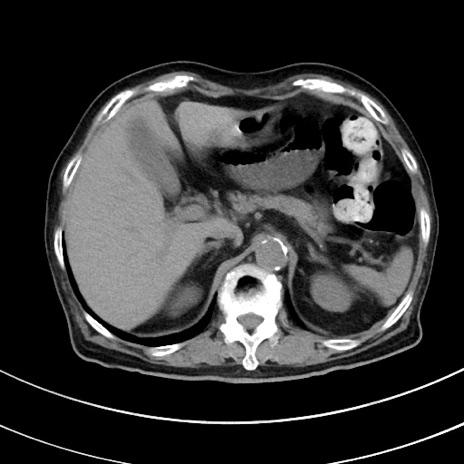

冠状断像

【症例】70歳代 女性

【主訴】心窩部痛

【現病歴】延髄病変の精査・加療にて神経内科入院中。本日より心窩部痛あり。

【身体所見】右下腹部を中心に圧痛と反跳痛あり。

【データ】WBC 10900、CRP 0.02